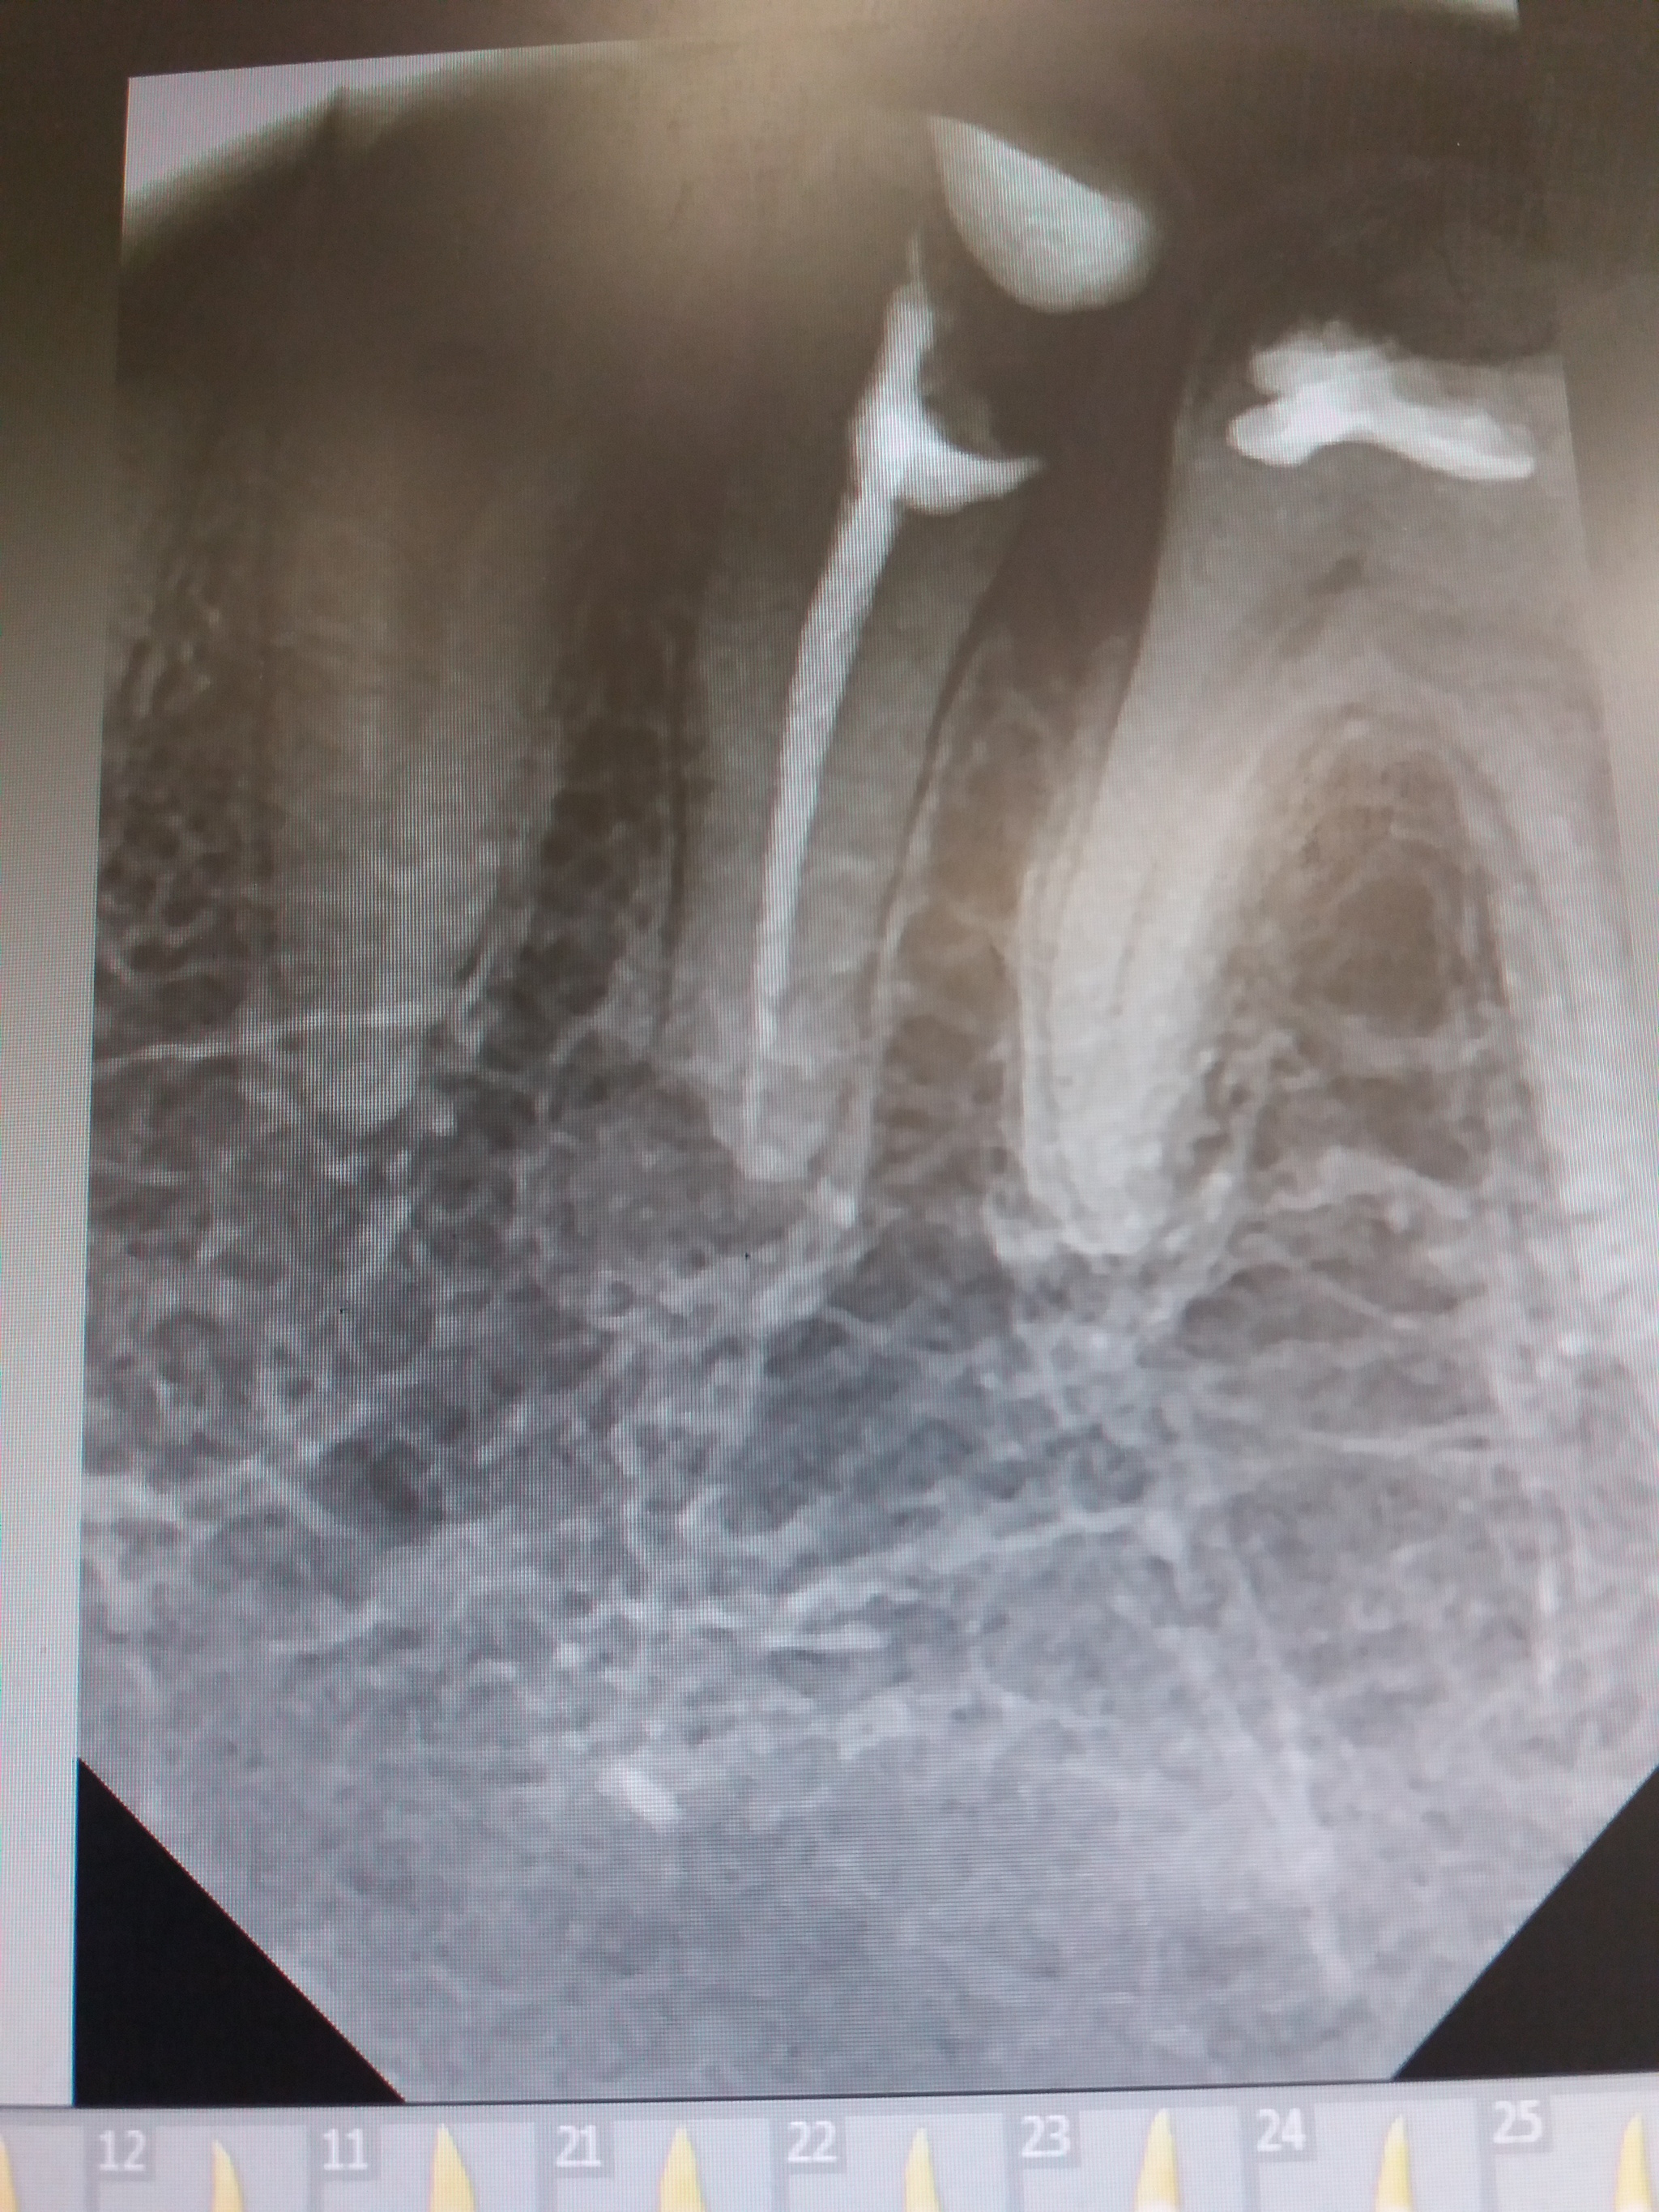

доброго времени суток, вопрос к лиге врачей, обнаружили кисту в зубе, можно ли вылечить терпевтически или же необходима резекция или удаление, ннсколько врачей спорят, хирург настаивает на резекции, один терапевт говорит что можно вытащить через канал, второй тоже настаивает на резекции